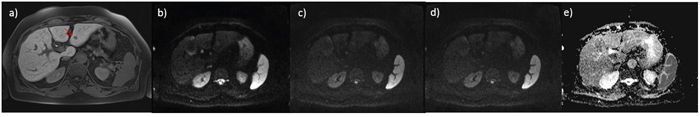

A total of 62 HCCs were evaluated (median 1.82 lesions; diameter between 12 and 20 mm). All tumors were histologically classified according to the major Edmondson-Steiner grade on final pathologic reports as follows: 14 with grade 1, 30 with grade 2, 18 with grade 3, and no one with grade 4. Figure 1, 2 and 3 report example of HCC of grade 1, 2 and 3 respectively.

Figure 2: small HCC on III hepatic segment G2; in a. VIBE T1 weighted image, in b. DWI image at b value 50 s/mm2, in c. DWI image at b value 400 s/mm2, in d. DWI image at b value 800 s/mm2 and in e. ADC map.